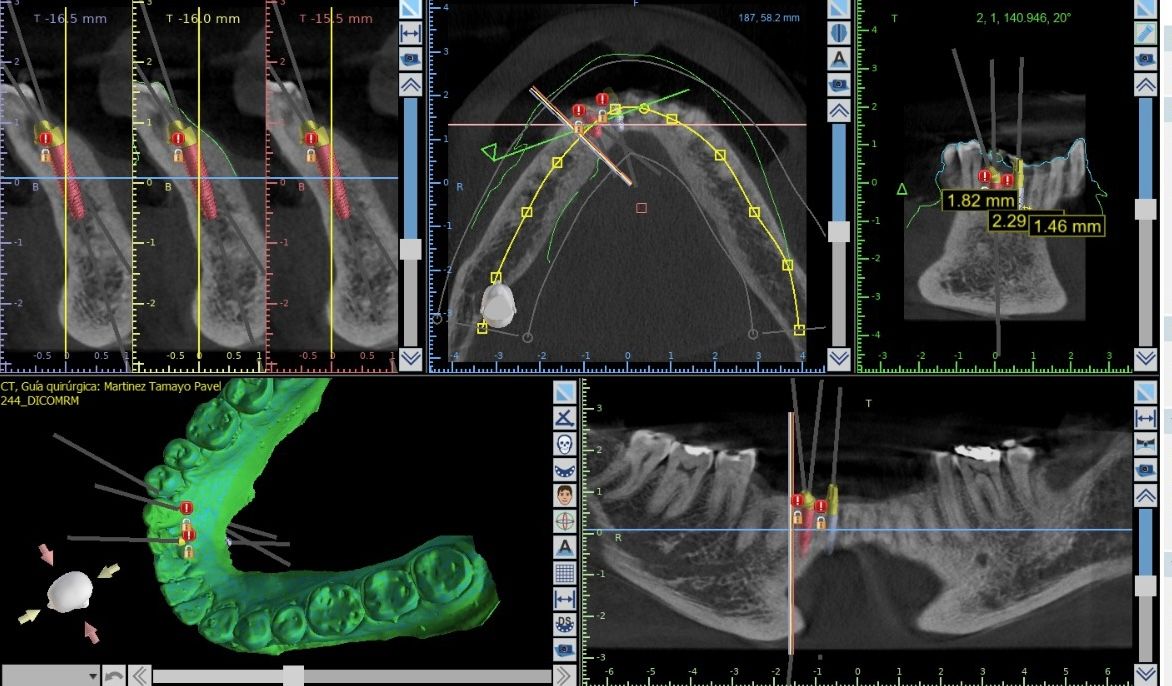

Cirujano Dentista Egresado de la Universidad Autonoma Villa Rica, Especialista en Periodoncia e Implantes Dentales de la Universidad Popular Autónoma del Estado de Puebla, Cursos de Actualización de Reconstrucción Ósea, Manejo de Tejidos Blandos Periimplantarios, Cirugía Guiada en la Colocación de Implantes Dentales, Carga Inmediata en Implantes Dentales, Rehabilitación de Implantes Dentales.

¿Que es un Implante Dental?

- Es un aditamento con forma de tornillo elaborado de titanio o de zirconio, que se inserta en el hueso a través de una pequeña cirugía, hasta que se osteointegre con el hueso y se coloque un provisional y posteriormente una corona definitiva.

-La ventaja de los Implantes Dentales es que sustituyen a los dientes o muelas perdidos sin que se tenga que desgastar los dientes adyacentes para un puente fijo.